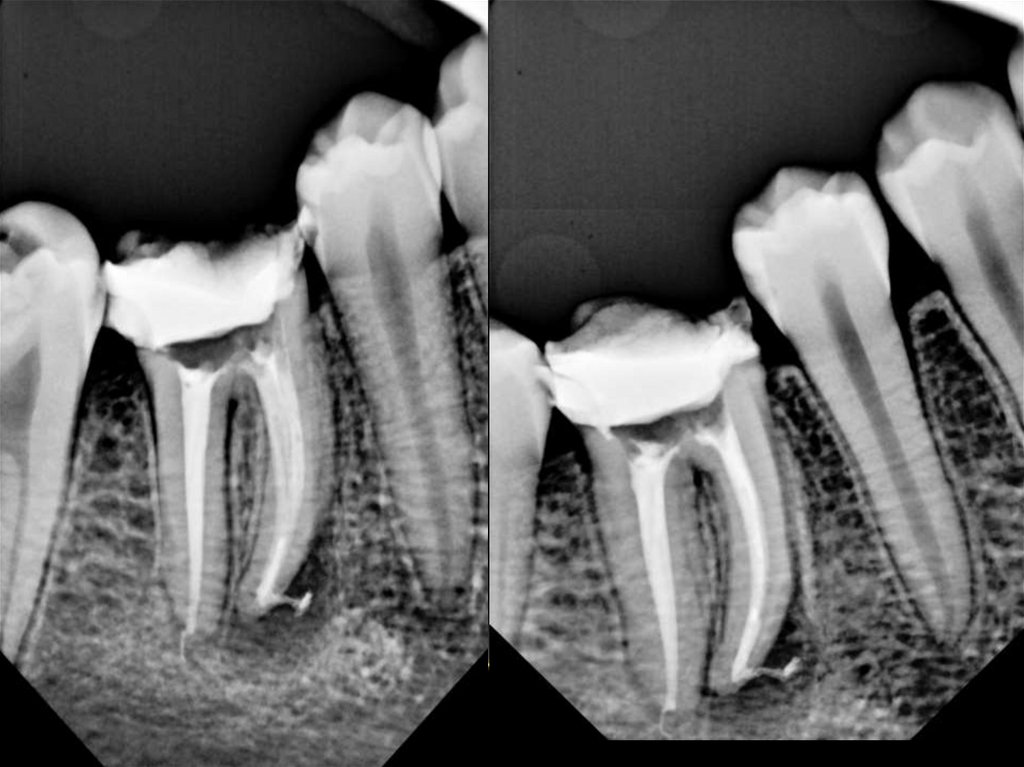

Методики пломбирования корневых каналов

Материалы для пломбирования корневых каналов

Пломбирование корневых каналов зуба

Лечение корневых каналов